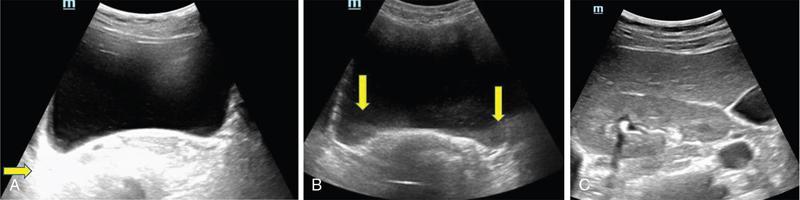

ULTRASOUND MALE PELVIS Vivek Kashyap Pelvic ultrasound is a noninvasive technique for imaging major organs in the pelvis including the bladder, prostate gland, blood vessels and bowel. It is usually the first line of investigation to evaluate the prostate and seminal vesicles. Ultrasound is a safe and reliable imaging resource to assess the pathology and guide towards appropriate treatment plan. To start pelvic ultrasound with evaluation of the shape and size of the bladder. The bladder is in the pelvis, posterior to the pubic bones. The peritoneum is seen superior to the urinary bladder and reflecting over the anterior surface. The trigone is a triangular area bounded by the two ureteric and urethral orifices. The urinary bladder has an outer loose connective tissue layer, known as subserosa which bounds the three muscular layers. The innermost is the mucosal layer. These layers should be smooth and uniform and the thickness will depend on the bladder distension. Prostate can be seen posterior to the urinary bladder when examined in transverse views. Prostate is seen at the inferior part of the urinary bladder in sagittal view (Fig. 11.1.1.1A). It should be examined in both the views. Urinary bladder neoplasms are usually seen arising from the walls of the urinary bladder, though these can be of varying shapes, usually are polypoidal and can present as solitary or multiple lesions, often seen on opposing walls of the urinary bladder, also known as ‘kissing lesions’ (Fig. 11.1.1.1B). For evaluating the bladder, it should be moderately filled. An overfilled bladder will cause patient discomfort and can compress structures posterior to it. The bladder should be scanned in the transverse and sagittal planes and prevoid volume is calculated. After micturition, the length, width and height (cm) of the bladder are recorded in sagittal and horizontal planes. The postvoid residual volume is calculated using the formula: Postvoid residual volume (PVR) = Length × Width × Height × 0.5 Normally there is no residual urine. PVR less than 50 is usually considered as insignificant. PVR volume more than 100 mL is considered significant in adults. Ureteric jets are the normal visualization of the physiological periodic efflux of urine from the distal ureter into the bladder. Ureteric jet can be appreciated by colour Doppler examination as a sudden burst of colour in the bladder that lasts for a few seconds. Bladder wall thickening is considered significant if >3 mm in a distended bladder and >5 mm in a collapsed bladder; however, it’s a good practice to fill the bladder completely before doing the investigation (Fig. 11.1.1.2). The common causes of bladder wall thickening include: Urinary bladder diverticula are examined very well on ultrasound (Fig. 11.1.1.2). Congenital diverticula, also known as Hutch diverticula are generally seen near the ureteral orifices. Acquired diverticula are generally due to bladder outlet obstruction. Bladder mucosa herniates through weak portions of the bladder walls, this may create diverticula with a narrow neck leading to urinary stasis, which may in turn cause stones, infection tumours or ureteric obstruction. These diverticula appear as an outpouching sac from the bladder and urine may be seen flowing into or out of the diverticulum. Intraluminal pathologies such as vesicle calculus are seen within the bladder, calcifications are seen in the bladder wall or in the mass lesions. Faeces, inflammatory or neoplastic bowel lesions, enlarged lymph node, masses from nerves, vessels and bones, ectopic or transplant kidney, accessory spleen can also be diagnosed from pelvic ultrasound. Ultrasound use for the male pelvis even though limited, has great importance to detect free abdominal fluid, undescended testes in the groin and hernias. Dilated urethra in posterior urethral valves, and occasionally a valve itself can be seen in real-time sonography, aided by transperineal scanning. Prevoid and postvoid volume Wall thickness Ureteric jets Size and volume Morphology of central and peripheral zone Morphology of seminal vesicles ULTRASONOGRAPHY INGUINOSCROTAL REGION V. Sivakumar Ultrasonography is the ideal noninvasive imaging modality for evaluation of scrotal abnormalities. It is capable of differentiating the most important aetiologies of acute scrotal pain and swelling, including epididymitis and testicular torsion, and is the imaging modality of choice in acute scrotal trauma. In patients presenting with palpable abnormality or scrotal swelling, ultrasonography can detect, locate and characterize both intratesticular and extratesticular masses and other abnormalities. A 12–17 MHz high-frequency linear array transducer provides excellent anatomic detail of the testicles and surrounding structures. In addition, vascular perfusion can be easily assessed using colour and spectral Doppler analysis. In most cases of scrotal disease, the combination of clinical history, physical examination and information obtained with ultrasonography is sufficient for diagnostic decision making. This review covers the normal scrotal anatomy as well as various testicular and scrotal lesions. Ultrasound is the widely used modality of choice for evaluation of scrotal abnormalities. Scrotal ultrasound is very helpful differentiating the most common causes of acute scrotal pain and swelling, including epididymoorchitis and torsion testis, and is the choice of investigation for acute scrotal trauma. Detection, localization and characterization of intratesticular and extratesticular pathologies are made easy using scrotal ultrasound. A 12–17 MHz high-frequency linear probe or transducer provides valuable anatomical information of testes and adjacent structures. Colour and spectral Doppler analysis can be used in assessing the vascular perfusion status of scrotal structures in real time. In most cases of scrotal disease, the combination of course, clinical history, clinical examination and imaging finding on ultrasound and Doppler is very essential in the diagnosis of scrotal diseases. Clinical examination sometimes leads to nonspecific signs and symptoms such as vague scrotal pain, suspicious scrotal mass or swelling. In such situations, ultrasound is useful in diagnosing and characterizing intratesticular and extratesticular pathologies as well as distinguishing benign or malignant lesions as well as identifying conditions requiring emergency surgical attention. Scrotum is a fibromuscular sac like structure divided into two hemiscrotum, right and left by a midline septum or raphe. Both the testes are located within the scrotum. The normal testicle appears like a ovoid structure with a homogeneous intermediate echogenicity and measuring approximately ~ 5 × 3 × 2 cm (craniocaudal, anteroposterior, width) (Fig. 11.1.2.1) Epididymis is elongated comma-shaped structure abutting posterior margin of testes and divided into three parts, head, body and tail. Epididymal head is seen in close relation to superior pole of testis and appears iso- to hyperechoic to the adjacent testicular parenchyma (Fig. 11.1.2.2). Epididymal body and tail can be visualized posterior to and along inferior pole of the testes and appears isoechoic to testicular parenchyma. A separate fibrous capsule called the tunica albuginea in each of the hemiscrotum encloses the testes and epididymis. This fibrous capsule can be noticed as a thin echogenic band like structure surrounding the testis on ultrasound. Tunica albuginea is covered by the tunica vaginalis, which is a remnant of processus vaginalis. It represents a closed sac of peritoneum and has two layers. The visceral layer of tunica vaginalis is seen lining the tunica albuginea of testis and is separated from the parietal layer that lines the inner aspect of the scrotal wall by minimal fluid-containing interspace. The tunica albuginea extends into the posteromedial aspect of testis to form the mediastinum testis (Fig. 11.1.2.3). It contains ducts, nerves and blood vessels. On ultrasound mediastinum is noticed as a thin echogenic band like structure. There are numerous fibrous septa extending from mediastinum testis dividing the testicle into multiple small lobules. The lobules are made of seminiferous tubules, they converge to form the tubuli recti, which are the testicular ducts that open into the rete testis. In around 20% of population, the rete testis can be visualized as a hypoechoic area adjoining the mediastinum testis. Efferent ductules coming out of rete testis can be seen draining into the epididymal head. From epididymal head, the ducts converge into a single duct in the epididymal body and exit the epididymal tail as the vas deferens. The vas deferens runs along the contents of spermatic cord and courses superiorly within the inguinal canal. The spermatic cord contains nerves, testicular artery, deferential artery, cremasteric artery, lymphatic ducts and the pampiniform venous plexus. On ultrasound the spermatic cord appears as an echogenic band like structure within the inguinal canal. The major vascular supply to the testes is by the paired testicular arteries which arise from the abdominal aorta. The testicular artery after entering into the tunica albuginea branches into capsular arteries and recurrent rami branches which then courses centrifugally into the mediastinum. A collateral circulation comprising of deferential artery and the cremasteric artery is also seen. Arterial supply to the remaining parts of the scrotum is from the pudendal arteries, which arise from the internal iliac artery. Anatomic relationships of the vascular structures within the spermatic cord are important and alteration in this normal relationship is associated with few pathologies. High insertion of tunica vaginalis to the spermatic cord, the bell-and-clapper deformity leaves the testes to rotate freely within the tunica and can lead to intravaginal testicular torsion. The pampiniform venous plexus continues as the testicular vein in the deep inguinal canal. The right testicular vein drains directly into the inferior vena cava (IVC) whereas the left testicular vein drains into the IVC via the left renal vein. Epididymal and testicular appendages usually represent embryologic remnants. They are better visualized in ultrasound in the presence of a hydrocele. The appendix of testis (hydatid of Morgagni) can be visualized as an isoechoic, oval structure between the epididymis and testis (Fig. 11.1.2.4). An appendix of epididymis is a pedunculated structure arising from the epididymal head, which is also isoechoic to testicular tissue. Ultrasound of the scrotum includes both greyscale and colour Doppler evaluation of testicles, epididymis on both sides and the scrotum. Spectral Doppler evaluation can be used to demonstrate normal waveforms in the testicular artery and vein. For scanning a high frequency, broad bandwidth 17–5 MHz or 12–5 MHz linear array transducer is used. With the help of a towel placed under the scrotum the testicles and scrotum are elevated. With another towel the patient retracts and covers his penis. Initially with a side-to-side large-field imaging both testes are demonstrated using both greyscale and Doppler techniques. Echogenicity and perfusion of each testis is examined. Each testis is imaged longitudinally in medial, mid, lateral portions and transversely in upper, mid and lower pole regions. Three-dimensional (3D) measurement of each testicle is taken (length, width and height). Epididymis evaluation includes longitudinal and transverse imaging including head, body and tail. Colour Doppler study of testes and epididymis is done on both sides and status of capsular and centripetal arteries assessed and documented. Spectral waveform of both arterial and venous flow is documented on each side. Optimization of colour and spectral Doppler analysis is done to clearly depict low velocity venous flow. Colour Doppler imaging in various planes and comparison with contralateral asymptomatic testis is done in specific evaluation for testicular torsion. Scrotal survey should be done for extratesticular findings such as hydrocele, varicocele or calcification/scrotolith. The pampiniform plexus of veins should be evaluated for the diameter and its augmentation on standing position or Valsalva manoeuvre. Scrotal wall should be assessed for thickening and oedema. Extratesticular and intratesticular pathologies, either focal or diffuse should be identified and characterized using grey scale and Doppler imaging techniques appropriately. Focal lesions should also be measured three dimensionally. Presence of solid, cystic, calcific, complex cystic areas in the lesion should be characterized. Labelling of the lesion/images in respect to location (upper, middle or lower), orientation (longitudinal and transverse) and position of the patient (supine, decubitus and standing) is done. Labelling of the lesion/images during specific manoeuvres such as Valsalva should also be done. For scanning a high frequency, broad bandwidth 17–5 MHz or 12–5 MHz linear array transducer is used. Initially with a side-to-side large-field imaging both testes are demonstrated using both greyscale and Doppler techniques. Echogenicity and perfusion of each testis and epididymis should be examined. Each testis is imaged longitudinally in medial, mid, lateral portions and transversely in upper, mid and lower pole regions. Epididymis evaluation includes longitudinal and transverse imaging including head, body and tail. Spectral waveform of both arterial and venous flow is documented on each side. Ultrasound and colour Doppler are the first-line imaging modality for acute or chronic scrotal pathologies. Ultrasound is a safe and reliable imaging modality for demonstration of scrotal anatomy, localization of testicular pathologies and for assessing the vascularity. Since most of the testicular pathologies have characteristic ultrasound appearance, ultrasonography is able to clearly guide patient management and prevent unnecessary surgery. TRANSRECTAL ULTRASOUND OF PROSTATE Vivek Kashyap Carcinoma prostate is the second most common cancer in the world and the sixth leading cause of cancer death in men. The worldwide burden of prostatic cancer is estimated to touch 1.7 million new cases and 499,000 deaths by 2030. The prostate is an unpaired glandular organ. The average dimensions in a healthy young adult is 3.75–4.00 × 2.5–3.00 × 3.1–3.8 cm (w × h × l) and the volume ranges from 20–25 cm3. It produces the prostate-specific antigen (PSA) a glycoprotein which is an ingredient of the semen and is responsible for liquefying semen. The prostate has endocrine properties as it produces prostaglandins E, F and A, spermidine and spermine. It is also the place of the conversion of testosterone into dihydrotestosterone under the influence of the 5-α-reductase enzyme. COMMON INDICATIONS FOR A TRANSRECTAL ULTRASOUND (TRUS) OF PROSTATE Assessment of prostate size Abnormal growth within the prostate Male infertility Elevated PSA levels Detecting disorders within the prostate Micturating difficulties Because ultrasound provides real-time images, it can be used to guide biopsies which may be necessary, FNAC or tissue biopsy as well as brachytherapy seed placements. Transrectal US is a widely used clinical imaging method. For confirming the diagnosis of prostatic cancer, a systematic needle biopsy with US guidance is the diagnostic test of choice (Fig. 11.1.3.1). To understand the images produced by transrectal US, it is important to understand the zonal anatomy of the prostate gland. The outer zone is the peripheral zone, inner to it the transitional zone, then central zone and periurethral zone. The peripheral zone is the largest, containing almost 70% of the prostatic tissue and is the site of most prostatic cancers. It is separated from inner zones by a surgical capsule which may be seen as hyperechogenic line The transitional zone is much smaller (about 5%) and is seen as two small glandular areas such as saddle bags adjacent to proximal urethral segment. The central zone constitutes almost 25%–30% of the total gland size. The ducts of vas deferens and seminal vesicles pass through this zone. This zone shows only about 5% incidence of cancers and appears relatively resistant to diseases. The periurethral zone is only about 1% and encircles the urethra. The commonest features of benign prostatic hyperplasia are hypoechoic enlargement of inner zone. Other features could be calcifications along with diffuse or well-circumscribed rounded hypoechoic or hyperechoic nodules along with degenerative or retention cysts (Fig. 11.1.3.2A,B). Well-circumscribed hypoechoic nodules arising in the transitional zone may become so large that they distort the gland and appear to be in the peripheral zone and these are invariably benign. In cases of hyperplastic nodules occurring in the peripheral zone, they will appear as firm to hard nodules and should undergo a biopsy. We must remember that prostatic enlargement may not correlate with urinary symptoms in all cases, therefore any urinary dysfunction calls for evaluation of the prostate, bladder, urethra, spine and CNS. Transvesicle ultrasound is done to evaluate prostate size, median lobe, bladder trabeculations, diverticula, tumours or calculi. Patients who have had TURP done before will invariably show a defect in the gland. However, the size of the defect will not always correlate with the amount of tissue removed during the procedure, nor does it correlate well with the success of the procedure. This is a condition of inflammation of the prostate and seminal vesicles. The prostate may appear normal in prostatitis or there may be a focal mass, ejaculatory duct calcification, irregularity or thickening of the capsule, periurethral glandular irregularity, dilated periprostatic veins and distended seminal vesicles. Chronic granulomatous prostatitis can present as diffuse large or small hypoechoic zones or a solitary hypoechoic lesion. The examination is generally painful and colour Doppler may show a very vascular focus (Fig. 11.1.3.3A). If we see a hypoechoic mass within the prostate with or without internal echoes may be an abscess. Common ones are degenerative or retention cysts in hyperplastic nodules. These are generally symptomless, unless they become large (Fig. 11.1.3.3B). Prostatic utricle cysts are in the midline and are caused by dilatation of prostatic utricle. These can be associated with unilateral renal agenesis and rarely contain spermatozoa. Other type of cysts seen are Mullerian duct cyst which are a little lateral and are also tear drop and do not contain spermatozoa. Ejaculatory duct cysts are small and could be a small diverticulum of the ejaculatory duct or an obstruction. These can be fusiform in shape with pointed ends and contain spermatozoa. These are associated with infertility. Seminal vesicle cysts are another type, which could be large and solitary, associated with ipsilateral renal agenesis sometimes. In cases of male infertility, transrectal sonography has an important role in assessment of causes of azoospermia for ejaculatory duct obstruction or anomalies (about 1%–2%) Seminal vesicles, dilated ejaculatory ducts and midline cysts can suggest obstruction. There is a strong association of absence of vas with cystic fibrosis. The results of transrectal scanning in infertile men with azoospermia can be normal appearance (25%), bilateral absence of vas deferens (34%), bilateral occlusion of the vas, seminal vesicles or ejaculatory ducts by calcification or fibrosis (16%), unilateral absence of vas (11%), obstructing cysts (9%), ductal obstruction due to calculi (4%). Some of these causes, more so in distal two-thirds could be surgically correctable and therefore it is essential that careful evaluation is done. Haematospermia is blood in the semen. This could be acute (red in colour) or dark brown (old blood). Nonspecific inflammation of the prostate or seminal structures is the most common cause, resolving on its own after some time. We should exclude tumours or infection of prostate or bladder. Transrectal scanning can detect calculi or cysts in the seminal vesicles or ejaculatory ducts (Fig. 11.1.3.4). Other causes includes vascular malformation or sometimes following a prostatic biopsy. Ultrasound elastography is an imaging technique for mapping tissue stiffness of the prostate gland. Two elastography techniques that have developed are strain technique, and second, shear wave technique. The tissue stiffness information provided by US elastography can improve the detection rate of prostate malignancy and provide guidance for biopsy. Prostate elastography has high sensitivity for detecting prostate malignancy and shows high negative predictive values, ensuring that few malignant lesions will be missed. Transrectal US has been used for local staging of prostate cancer in some studies but is generally considered insufficient. Extracapsular extension (ECE) can be demonstrated by the bulging or irregularity of the capsule adjacent to a hypoechoic lesion. Seminal vesicle invasion (SVI) is diagnosed by demonstrating the extension of a lesion at the base of the prostate into a seminal vesicle. Solid hypoechoic lesions within the seminal vesicles or asymmetry of the seminal vesicles are indirect indicators of disease extension. Additional transrectal US-guided biopsies of the seminal vesicles can be performed when extra prostatic extension into the seminal vesicles is suspected. Studies performed in the 1980s showed when cancers are larger (stage T3) and more readily palpated, sensitivity for detecting ECE and SVI by transrectal US was more than 80%. With advent of colour duplex and power Doppler US, there has been renewed interest in the use of transrectal US to identify cancer in hyper vascular areas, with only modest improvements in sensitivity and specificity. Transrectal US continues to play an important role in therapy for directing brachytherapy seeds into the accurate location within the prostate. Cryotherapy and focal ablation of the prostate cancer also requires transrectal US guidance. Future developments in transrectal US may include the utilization of microbubble contrast agents and targeted imaging. Microbubbles coated with surface ligands that preferentially target tumour neovascularity can be used. Because of the large size of these bubbles (1 m), these agents can provide information about large-vessel microvascularity which can be useful in detecting cancer; however, if in future smaller-size microbubbles are available, they can further improve detection. Seminal vesicles have symmetric appearance and lie cephalic to the prostate and posterior to the bladder. They have a typical ‘bow-tie’ appearance in transverse scans, and a club or tennis-racket shape in longitudinal scan. They show homogenously fine echoes but less echogenic than prostate. Volume of seminal vesicles tends to shrink after the fifth decade. TRUS provides excellent anatomical details of seminal vesical and ejaculatory ducts. TRUS helps to diagnose calculi in seminal vesicle or ejaculatory duct. Also TRUS provides high-resolution imaging of the prostate, seminal vesicles and vas deferens and is the investigation modality of choice in diagnosing congenital and acquired abnormalities implicated in the cause of obstructive azoospermia. USG FEMALE PELVIS M. Alamelu Ultrasound is a noninvasive, easily available and informative investigation. A skilfully done and well-interpreted ultrasonogram image usually obviates the need to proceed to additional expensive and composite cross-sectional imaging tests. Ultrasound is high-frequency sound waves (20 kHz), inaudible to human that can be safely transmitted into human body to scan the tissues. Images produced in ultrasound depend on the mechanical properties of tissues and their distance from the source of the sound as it will differentially affect the energy of the sound waves (Table 11.1.4.1). As the frequency of the transducer scan-head increases, the resolution increases and penetration into the body tissue decreases. The piezoelectric crystals convert electric energy into mechanical energy and sound waves are produced. Pelvic pain Pelvic masses Dysmenorrhea (painful menses) Amenorrhea Abnormal uterine bleeding Follow-up of previously detected abnormality Infertility Pelvic infection Evaluation after pelvic surgery, delivery or abortion To localize intrauterine device (IUD) Screening for genital tract malignancy in high-risk patients Pelvic organ prolapse The transducer is placed longitudinally over the adequately distended bladder, the gain settings to be adjusted for optimal visualization (Fig. 11.1.4.1). Scanning is to begin longitudinally from midline between umbilicus and pubic symphysis, angulated to the sides, moved laterally to both right and left side (Fig. 11.1.4.2). Next, scan transversely beginning from pubic symphysis down to umbilicus upwards (Fig. 11.1.4.3). If needed, patient can be asked to turn obliquely (30–40 degrees) for evaluation of ovaries and adnexa (Fig. 11.1.4.4). The following should be assessed: The overall length of uterus is evaluated in the sagittal view from fundus to cervix (to the external os, if seen). The length can either be measured as a straight line from fundus to cervix by using the outer-to-outer technique or can be measured from fundus of uterus along the endometrial lining and endocervical canal using the outer-to-outer technique (Fig. 11.1.4.5). The anteroposterior measurement of the uterus is made in the sagittal view from its anterior to posterior uterine walls. The maximum width can be measured in the transverse or coronal plain. The cervical component should be excluded from uterine length measurement for volumetric assessment of uterine corpus. The neonatal uterus, with exposure of maternal hormones is well depicted with US. The uterus is more narrower and shorter, with a mean length of 3 cm in infants of 4–12 months. Cervix attains a tubular shape and is proportionate to the uterine body. After 1 year of age, uterine length gradually increases and rapid growth occurs as the girls approach puberty. The mean uterine length 3 cm or less for young girls, 3–4.5 cm for prepubertal girls and 5–8 cm for pubertal girls. During puberty, the uterine body becomes more thicker and rounded, pear shaped, with a ratio of uterine body-to-cervix – 1.5:1, an appearance similar to that in women of reproductive age (Table 11.1.4.2). Source: J.E. Langer, E.R. Oliver, A.S. Lev-Toaff, B.G. Coleman, Imaging of the Female Pelvis through the life cycle, Radiographics 32 (2012) 1575–1597. H.J. Paltiel, A. Phelps, US of the pediatric female pelvis, Radiology 270 (2014) 644–657. Depending on the extent of the urinary bladder distension the normal uterus assumes a number of positions. Depending on the relationship of the angle of the long axis of the uterine body to the long axis of the cervix (flexion) and the long axis of the uterus to the long axis of the vagina (version) various positions are described. The most common position for uterus is in anteversion and anteflexion (Fig. 11.1.4.6). When the uterus is positioned in retroversion or retroflexion, it will be difficult to image transabdominally in most cases and is imaged well with an endovaginal transducer. Following every delivery, the uterus of parous women becomes more thick and round. After caesarean delivery, the uterus typically appears more elongated with variable deformity or thinning at the site of the lower uterine incision. The postmenopausal uterus is atrophied and small. The reduction in uterine size is most rapid during the first decade after menopause. The range can vary between 3.5 and 6.5 cm in length and 1.2 and 1.8 cm in anteroposterior dimensions. The endometrium should be assessed for the thickness, presence of focal abnormalities, its echogenicity, and the characteristics of fluid or masses in the cavity. The endometrium has a variable echogenicity, depending on its water content and the cellular density, that varies with the hormonal status of the patient. Neonatal uterus – The endometrium appears as echogenic line and endometrial fluid is often seen, due to residual effect of maternal hormones. The endometrium becomes less obvious, a thin echogenic line seen centrally in only 50% of girls of prepubertal age. The postpubertal endometrium is easily visible with transabdominal US and varies in thickness with the phases of the menstrual cycle. The thickness of endometrium correlates with the histologic changes to the estrogenic stimulation. The endometrium has a trilaminar appearance in preovulatory phase of menstrual cycle, then thickness becomes homogeneous after ovulation. The thin central hyperechoic line is not an endometrial layer it represents the interface between the anterior and posterior endometrial aspects. It should demonstrate as a continuous line on imaging parallel to the long axis of the uterus. Disruption of the central echogenic line, or any heterogeneity of the endometrium, indicates an underlying intracavitary lesion such as polyp, myoma or adhesion (Fig. 11.1.4.7). Progressively increasing echogenicity of the functional zone (compactum and spongiosum) seen with completion of the preovulatory phase and during the secretory phase. The homogeneously echogenic endometrium of the secretory phase poses difficulty in visualization of the central interface. For this reason, assessment of the focal abnormalities in endometrium is best done in the early phase of the menstrual cycle. The thickest part of the endometrium to be measured perpendicular to its longitudinal plane in the anteroposterior diameter, using the outer-to-outer technique, from echogenic to echogenic borders. The endometrial thickness is correctly measured from the anterior endometrial–myometrial interface to the posterior endometrial–myometrial interface. The adjacent myometrium (hypoechoic) and fluid in the cavity should be excluded in the measurements. The junctional zone thickness can be up to 12 mm (Fig. 11.1.4.8). In the women taking oral contraceptive pills or using other hormonal contraceptives, such as progesterone-releasing intrauterine devices, the endometrium is generally thin throughout the entire menstrual cycle. If the patient has an IUD, its location should be documented. Sonohysterography is an effective adjunct to further clarify an abnormally thickened or an incompletely visualized endometrium. The normal myometrium has three layers. The innermost layer is thin, relatively hypovascular and hypoechoic and is referred as the subendometrial halo. The next is the intermediate layer. It is the thickest layer and has uniform echotexture. The outer layer is also thin and slightly hypoechoic. The outer and the intermediate layer is separated by the arcuate vessels. These arteries again branch into radial arteries which penetrate through the intermediate layer and reach the inner layer. In some women the arcuate vessels (the veins) can be prominent and mimic cystic changes. During the reproductive ages, the normal uterine myometrium has homogeneous echogenicity with smooth margins. The nongravid uterus can demonstrates myometrial contractions, directed from the cervix to the fundus in the periovulatory phase, presumably to promote sperm transport, have been shown to have higher rates of successful fertilization compared to women with uncoordinated or absent wave activity. Postpartum uterus – the arcuate arteries undergo calcification, which can be seen earlier in diabetic women. This is a part of normal aging process. At times, small hyperechogenic foci are seen in inner myometrium, a few millimetres in size and nonshadowng in appearance, which represent dystrophic calcifications and have no clinical significance. The myometrium and cervix should be analysed for contour changes, echogenicity, masses, cysts and the symmetry between its anterior and posterior segments. The size and location of any pathological lesions should be measured in at least two dimensions. The normal postpartum uterus: The appearance of cervix varies with age of female. The cervix can be visualized as cylindrical-shaped structure on sagittal views and round/oval on coronal view. An echogenic central line denotes the interface between the two mucosal layers. Endocervical canal is 2–4 mm in single-layer thickness and in the centre it has a small amount of anechoic fluid or mucus. The plicae palmatae appear as serrations in the mucosa due to compact folds. The cervical stroma usually has similar echogenicity to myometrium and may demonstrate a narrow hypoechoic submucosal zone. Colour Doppler US shows little or no vascularity in the cervix. US beam is swept through the entire length of the cervix, from the internal os through the external os and upper vagina and laterally through the cervix including the bilateral parametrial and other adjacent pelvic tissues. This provides better, delineation of the cervical borders and the extent of any lesions. In case of any abnormality in the cervix identified at US, use of transducer pressure is extremely beneficial to determine if the lesion is located in the endocervical canal is arising from the stroma or from the cavity, particularly in case of a pedunculated intracavitary myoma or pedunculated polyp. On application of transducer pressure over the cervix, the intracavitary lesion may show mobility if a lesion is from the cavity mucosa, whereas lesions arising from the cervical stroma will be fixed in position despite the transducer pressure. The neonatal cervix is disproportionately large and bulbous on imaging. With increasing ages, the cervix becomes proportionate to the uterine body, producing a tubular shape. The branches of the uterine arteries can be identified on both sides of the cervix at colour Doppler flow imaging. The vagina seen as a collapsed tubular structure, distal to the uterine cervix and inferior to the urinary bladder. Caution: overdistension of the urinary bladder may cause urine accumulation in the vagina, misinterpreted for vaginal cysts. The presence of tampons or menstrual blood should also be looked. The adnexa include the ovaries, fallopian tubes, supporting ligaments and peritoneal folds of the lateral pelvis and the blood vessels. The adnexal mass lesions to be analysed for its position, relationship to the ovaries and uterus, size, shape, sonographic characteristics. The ovaries are demonstrated by scanning in transverse or longitudinal planes. They are seen lateral to the uterine corpus. The position of the ovary varies with the length of the infundibulopelvic ligament, presence of adhesions and any other anatomic abnormalities that displaces the ovaries. In neonates, the ovaries generally are easily imaged transabdominally as they are located above the true pelvis. As the child grows, the ovaries are embedded deeper in the pelvis, adjacent to the uterus. Ovarian size is to be measured in three dimensions (longitudinal, transverse and anteroposterior diameters) on views obtained in two orthogonal planes for the calculation of ovarian volume. Normal ovarian volume: simplified formula for volume calculation is 0.5 × length × width × thickness (Table 11.1.4.3). Follicles in ovaries in women of reproductive age can be demonstrated as echo-sparse, well-circumscribed areas within the ovarian stroma with varying sizes between 5 and 20 mm. Follicles are simple cysts with size of 9 mm or less. Ovarian mimics: The addition of 3D ultrasound is used to differentiate ovarian multiseptated cysts from hydosalpinges. Fallopian tubes are tubular structures extending from posterosuperior aspect of the uterine fundus. They open into the peritoneal cavity. Bilateral tubes are located in the superior edge of the broad ligament. They are 10–12 cm in length and 1–4 mm in diameter. A fallopian tube has four anatomic segments. The interstitial or intramural segment is located at the uterine cornua, within the myometrium. The isthmic segment is the narrowest portion of the fallopian tube. The ampullary segment is closer to the ovary, and constitutes around one-half of its total length. The infundibulum is funnel-shaped lateral most segment. The free edge of fallopian tube is composed of around 25 finger-like projections, called fimbriae. The fimbriae are suspended over the ovary and capture the ovum after its release. The fallopian tube is difficult to visualize in its normal state in USG. Fallopian tubes are frequently visualized in pathological conditions such as hydrosalpinx or neoplasm, the tube may be more clearly defined. Transvaginal ultrasonography is a better imaging modality for tubal visualization. The urinary bladder usually is a landmark for anatomic orientation in transvaginal and transabdominal scanning. Overdistension of the bladder will displace the uterus too posteriorly to hinder adequate imaging and also the patient will experience gratuitous discomfort. Conversely, in case of insufficient bladder filling, the posterior uterine wall or fundal lesions can be missed. Caution: a full bladder mimics a unilocular, anechoic pelvis cyst. In doubt cases, a postvoid scan is to be suggested for definitive evaluation. The bilateral urethrovesical junction and the distal urethra can be visualized in an adequately filled bladder. The cul-de-sac is posterior to the uterus and is to be evaluated for the presence of free fluid or loculated fluid and any mass lesions. Minimal free fluid (usually less than 1 cm in thickness) in the cul-de-sac is considered an unremarkable finding in girls of prepubertal ages and women of reproductive age. Artefacts are echoes that are falsely imaged without a corresponding anatomical structure (Fig. 11.1.4.9).